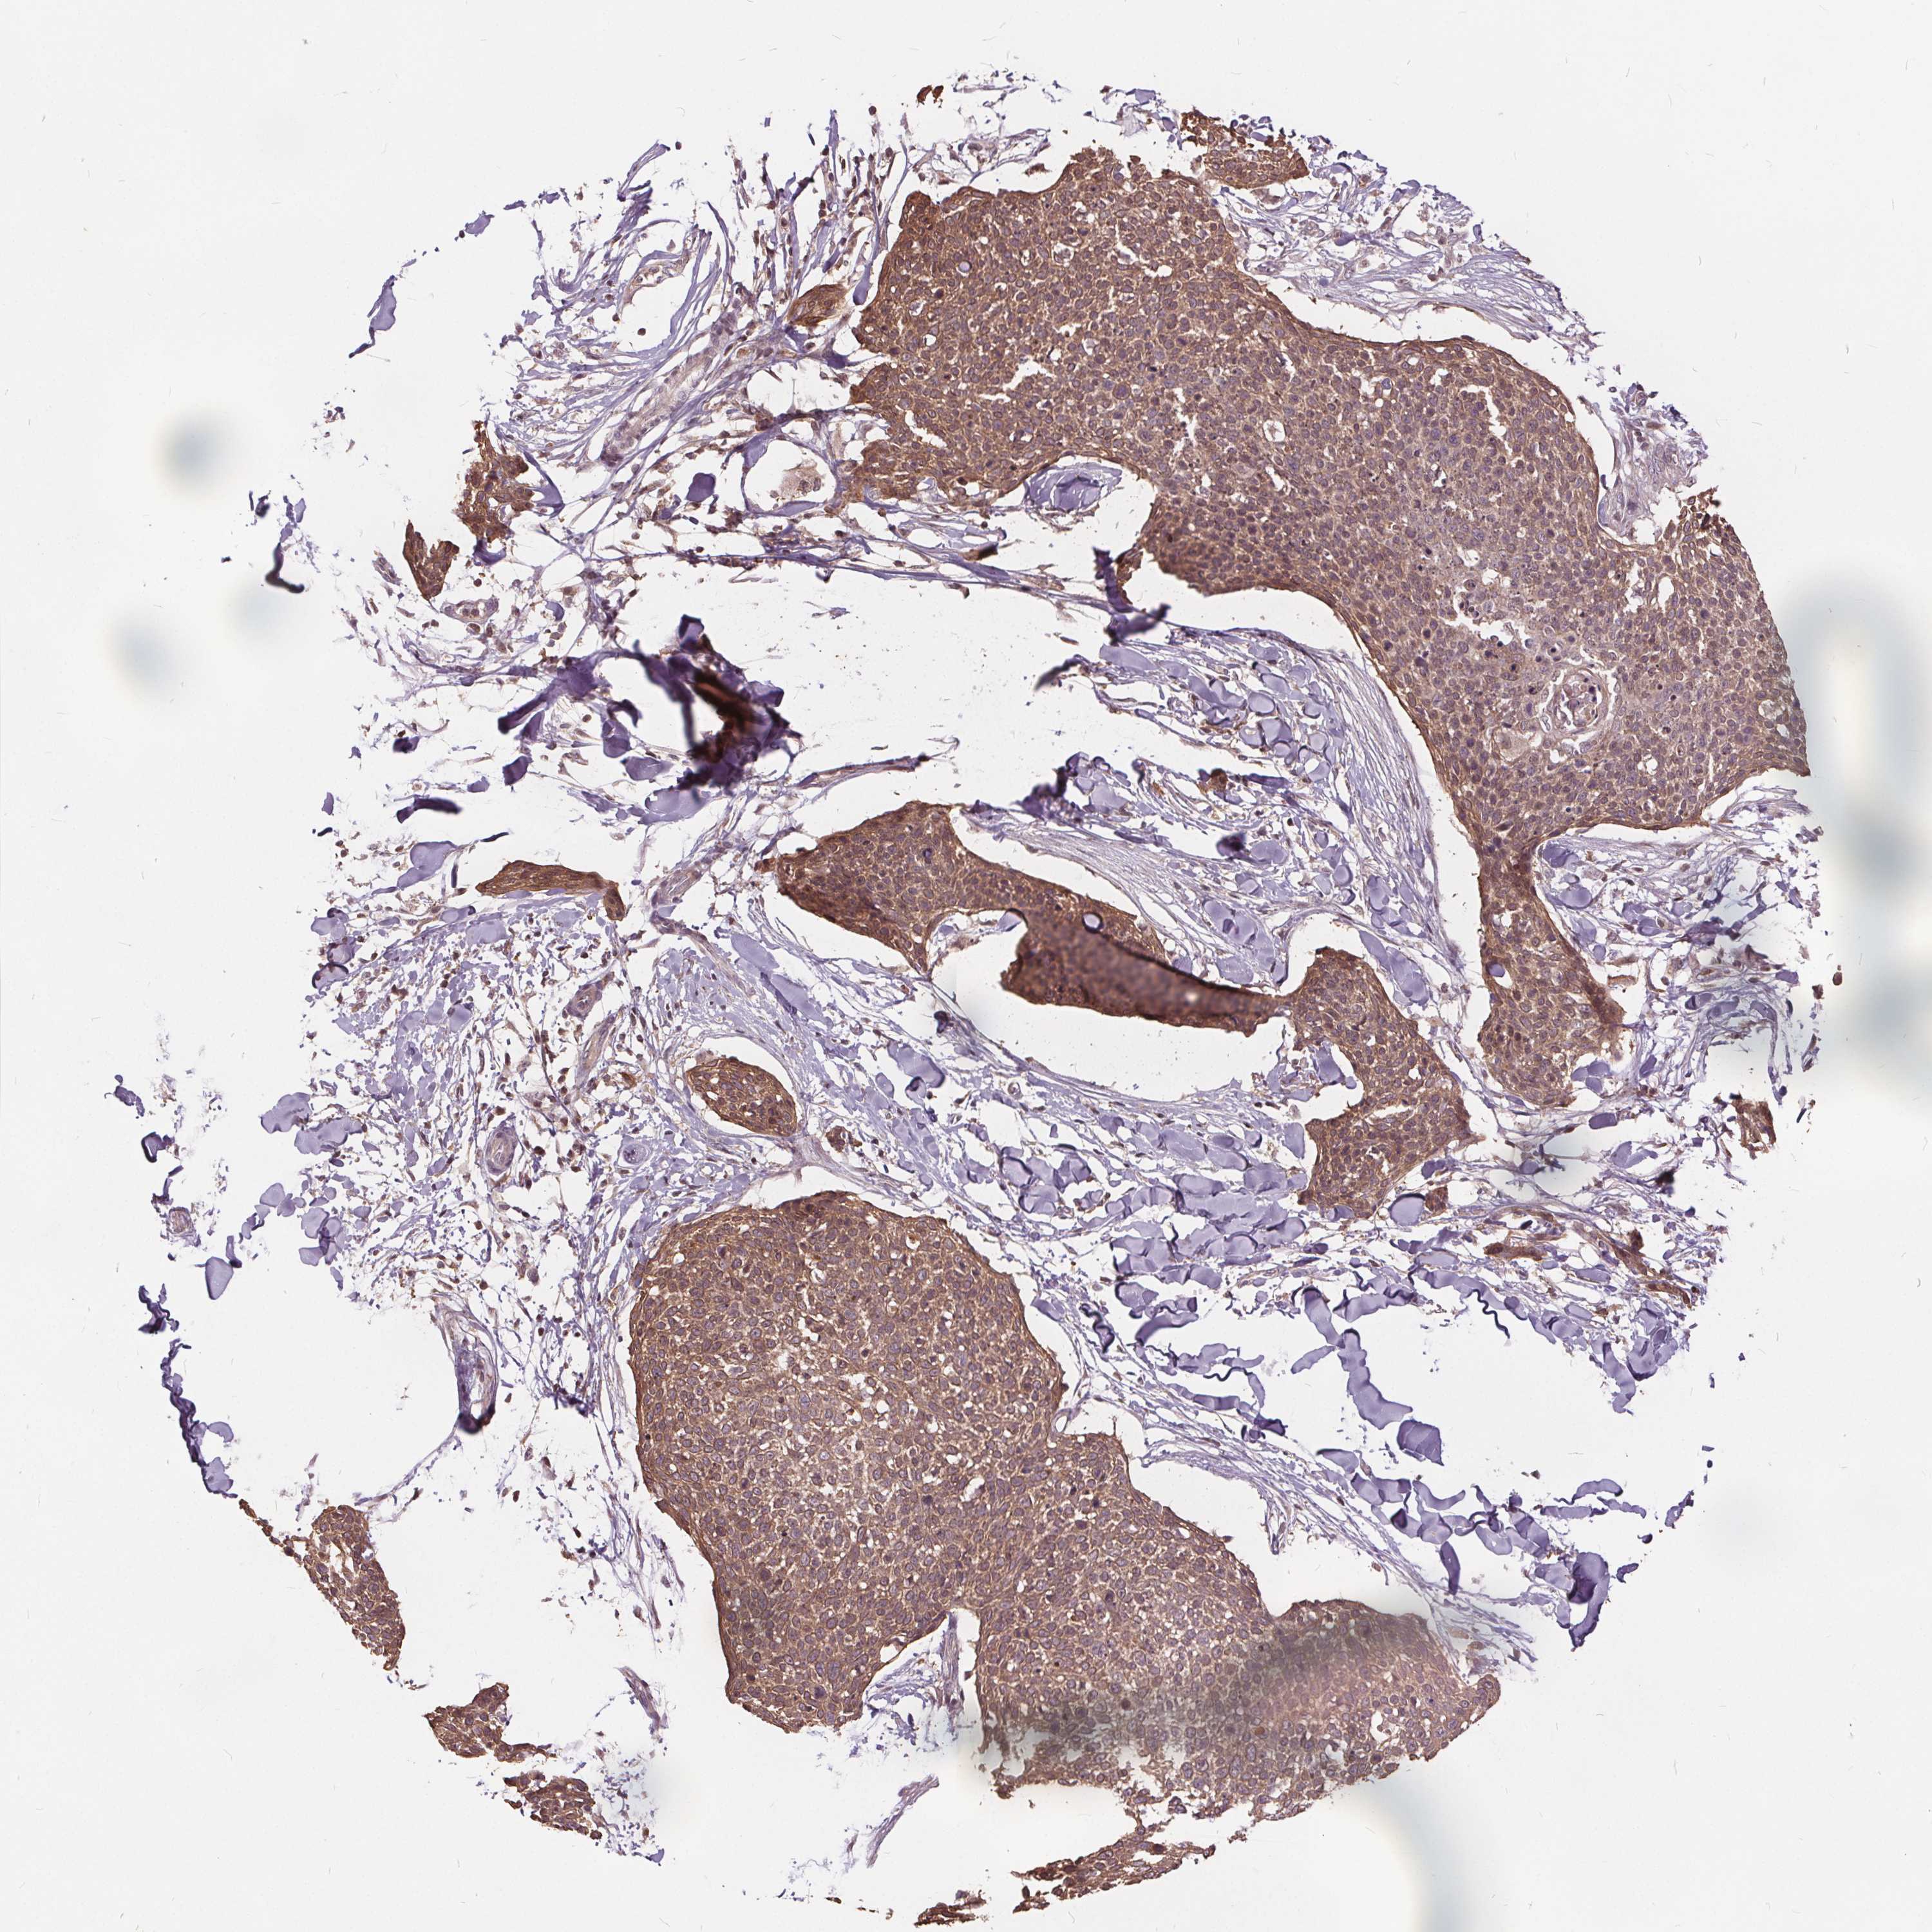

SKIN CANCER - Protein expressioni

A mouse-over function shows sample information and annotation data. Click on an image to view it in a full screen mode. Samples can be filtered based on level of antibody staining by selecting one or several of the following categories: high, medium, low and not detected. The assay and annotation is described here.

Each image is clickable and will lead to virtual microscopy that enables deeper exploration of all samples and also displays staining intensity scores, fraction scores and subcellular localization as well as patient and tissue information for each sample.

Antibody HPA065302

Antibody CAB069903

Basal cell carcinoma

Squamous cell carcinoma, NOS